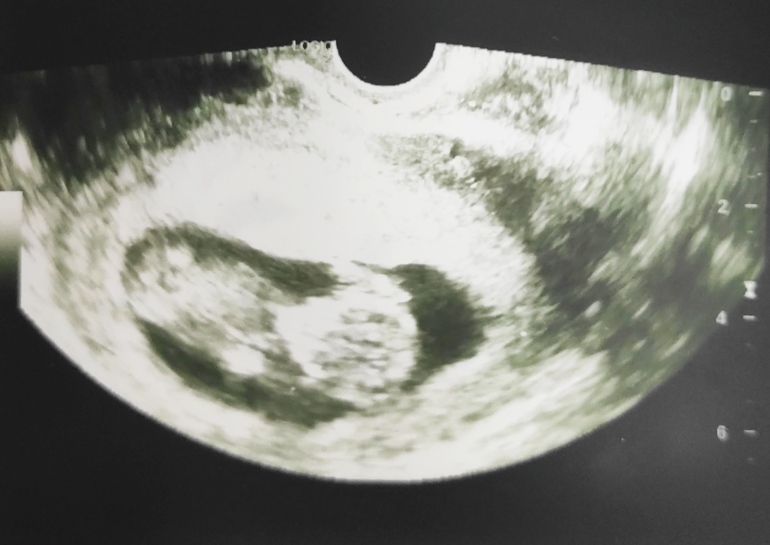

УЗИ, КТГ, доплер11 недель 4 дня.

Сделала УЗИ чтобы показать ребенка мужу)

Сердечко не послушали, зато посмотрели как шевелится, какие размеры. Разрешили снимать видео с монитора. Муж в восторге))))

УЗИстка с юмором, всë мужу показывала, комментировала, даже пол предположила: говорит на мальчика похоже.

Но мы пока не верим))

Срок пока маленький, поэтому ждём срок побольше.